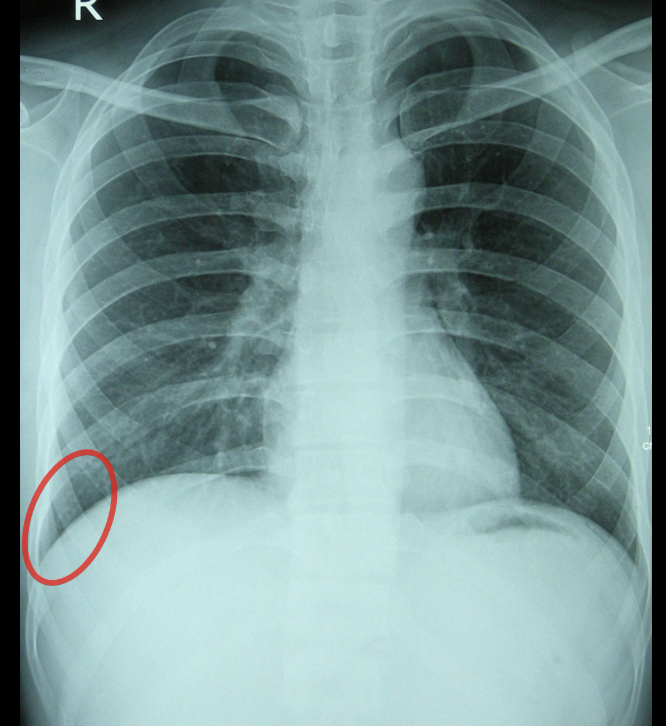

Thoracic cavity

Structure

info{costodiaphrag-matic recess}

CT